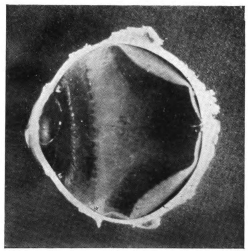

PLATE III.

16.

ABUNDANT EXUDATE INTO VITREOUS CAVITY

curly bracket span

42

17.

LENS FIRMLY FIXED BY ORGANIZED EXUDATE

18.

LENS FIRMLY FIXED BY ORGANIZED EXUDATE, BUT IN UNUSUAL POSITION

19.

TOTAL DETACHMENT OF RETINA, WITH CYST FORMATION

20.

RECLINED LENS LYING IN FRONT OF THE HYALOID BODY

21.

RECLINED LENS LYING IN FRONT OF THE HYALOID BODYxii